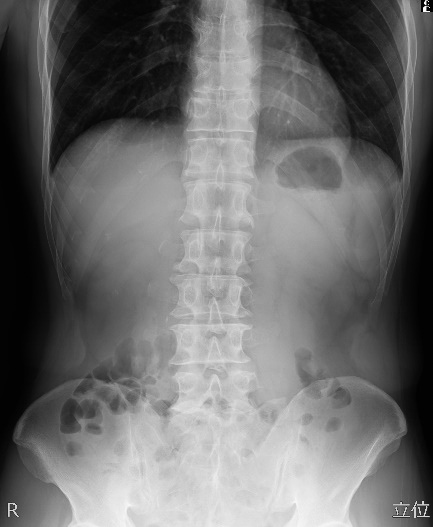

【一般撮影】

撮影部位にX線を照射し、その透過像を画像化する一般的なレントゲン検査のことです。当院では、「FPD(フラットパネルディスプレイ)システム」を導入しており、画像処理により迅速に高精度な画像を提供することができます。